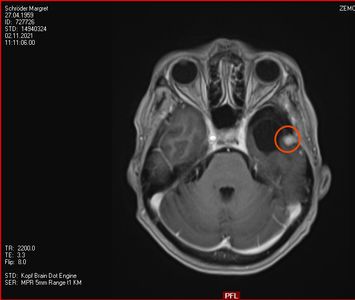

Am 03. November war mein Kontrollbesuch beim MRT. Leider ist ein kleiner Befund aufgetaucht. Schau das Video, dann kannst Du sehen.

Nun kann sich zeigen, ob die menschliche Medizin eine Lösung für mich hat. Möglichkeiten gibt es. Sogar mindestens eine, die der Neurochirurg als fein und elegant beschreibt. Gamma-Knife, eine Strahlentherapie. Klingt etwas nach Star Wars – man wird sehen,  etwas abwarten ist auch drin.

2. November 2021: Leider etwas gewachsen

Heute war ich im MRT im Bremen. Der Befund des auswertenden Arztes ist, dass er der Meinung ist, dass der Tumor etwas gewachsen ist. Ich habe mir die Bilder angesehen und versucht diese Aussage zu verstehen. Vermutlich ist sie richtig, aber das Wachstum ist nicht heftig nur vielleicht von 0,7 cm auf 0,8 cm. Aber Gamma-Knife hat es offensichtlich nicht entfernt.

In der nächsten Woche gehe ich mit denm Bildmaterial zum Neurochirurgen und der wird bei der Auswertung und der daraus folgenden notwendigen Konsequenzen sicher einen Rat haben. Solange muss ich mal abwarten.